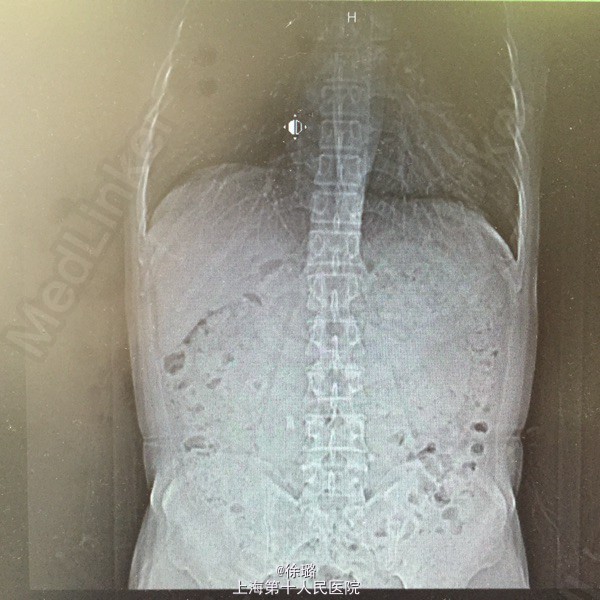

患者XXX,男,52岁。 主述:腰部酸胀不适半年余。 病史:患者半年前始无明显诱因出现腰部酸胀不适,左侧腰部酸胀稍明显,无恶心呕吐,不伴发热、黄疸、腹泻、黑便及肉眼血尿,症状轻,未诊治,今患者至当地医院查体,查B超示:双侧输尿管扩张伴肾积水,双侧输尿管上段结石。患者为进一步治疗,来我院就诊,拟“双侧输尿管上段结石”收住入院。

查体:双肾区无明显膨隆,左肾区无明显压痛,叩击痛可疑阳性,右肾区无明显压痛,叩击痛阴性,左侧输尿管走行区下段叩击痛阳性,右侧输尿管走行区下段叩击痛阴性,膀胱区无充盈,无压痛,尿道口无红肿。前列腺指检:前列腺未及增大,质韧,无明显结节,压痛阴性,指套无血染。 辅检:B超示:双侧输尿管扩张伴肾积水,双侧输尿管上段结石。尿路平片:1.双侧输尿管上段走行区致密影,考虑输尿管结石可能。2:盆腔耻骨联合上方投影区钙化影,前列腺钙化?请结合其他检查。3.CT:两侧输尿管上段结石,致其上输尿管及肾盂肾盏明显扩张积液。